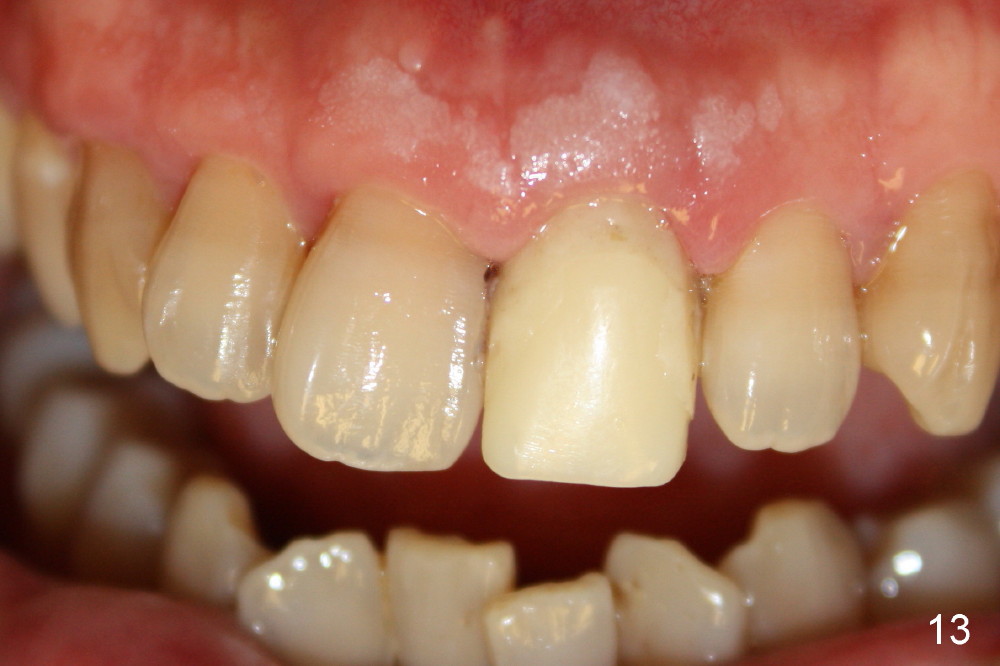

Bone expansion allows the implant (Fig.9 I) to have primary stability (insertion torque between 50 and 60 Ncm), since the cortex of the incisive canal is apparently intact. Allograft is placed in the labial gap (Fig.10, 11 *) following installation of the abutment (A). Finally an immediate provisional (Fig.10,12 P) is cemented. Fig.13,14 are taken 8 days postop. The patient returns 3 months postop (Fig.15,16). Osteointegration appears to have occurred (Fig.15 arrowheads) and is more obvious 9 months postop (Fig.17).